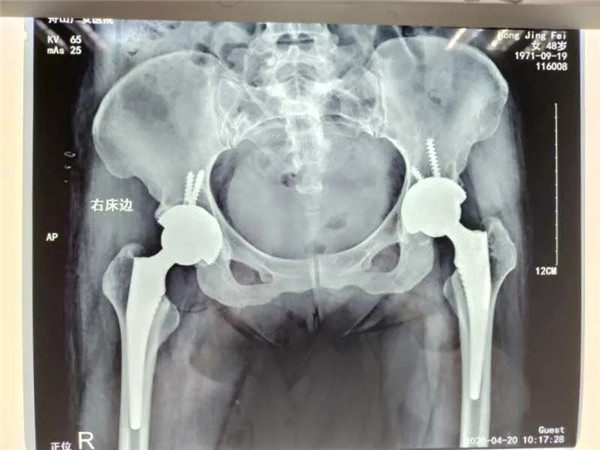

2017年5月,在朋友的建議下,洪女士來到我院,經(jīng)CT診斷雙側(cè)股骨頭無菌性壞死。便在危立軍副院長的建議下,做了左髖關(guān)節(jié)置換術(shù)。術(shù)后,洪女士恢復(fù)良好。

4月13日,危立軍副院長為洪女士實(shí)施了右側(cè)髖關(guān)節(jié)置換術(shù),手術(shù)在關(guān)節(jié)鏡下完成,術(shù)后洪女士感覺良好。術(shù)后一周,洪女士便可以下地行走。目前,洪女士恢復(fù)良好,已經(jīng)出院回家休養(yǎng)。

雙側(cè)髖關(guān)節(jié)置換

值得一提的是,對于此次手術(shù)的人工關(guān)節(jié)材料,洪女士仍舊和三年前一樣,選擇了全陶瓷人工關(guān)節(jié)。